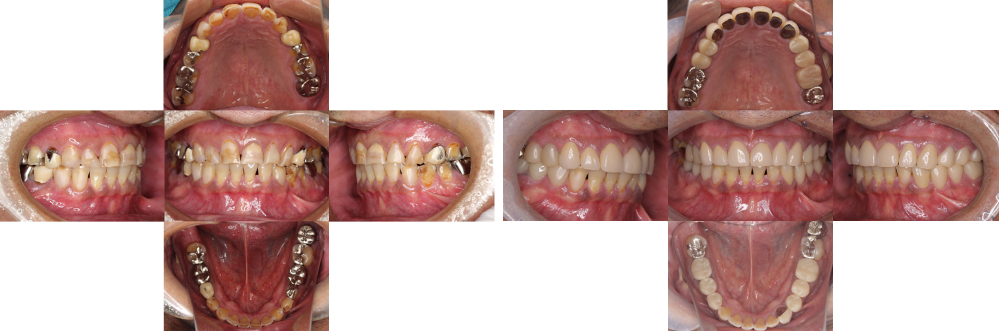

成人矯正

術前

術後

| 治療内容 | 掲載準備中 |

|---|---|

| 治療期間・回数 | 掲載準備中 |

| 費用 ※自由診療となります |

掲載準備中 |

| リスク・副作用 |

|